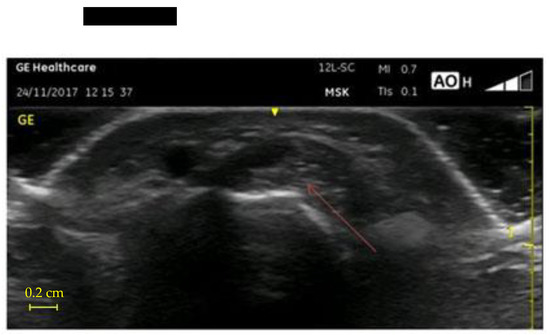

- UI of the hand-wrist area, performed with portable ultrasound device (Venue Scan, Venue 40, GE Healthcare®, Chicago, IL, USA) that allowed the researchers to store the examinations for further evaluation and discussion with other hospital experts in the final evaluation of all cases. A trained sonographer performed the wrist ultrasound. According to the European Society of Musculoskeletal Radiology’s protocol (ESSR) [23], acoustic windows were investigated in both the dorsal wrist, focusing on the extensor tendons and the radiocarpal joint, and the ventral wrist, focusing on the flexor tendons and the median nerve (Table 1).

| US cross-sectional area >0.10 cm2 | |||

| Dominant hand | 12 (32%) | 31 (81.5%) | p < 0.001 |

| Non-dominant hand | 10 (25%) | 21 (55.2%) | p = 0.008 |